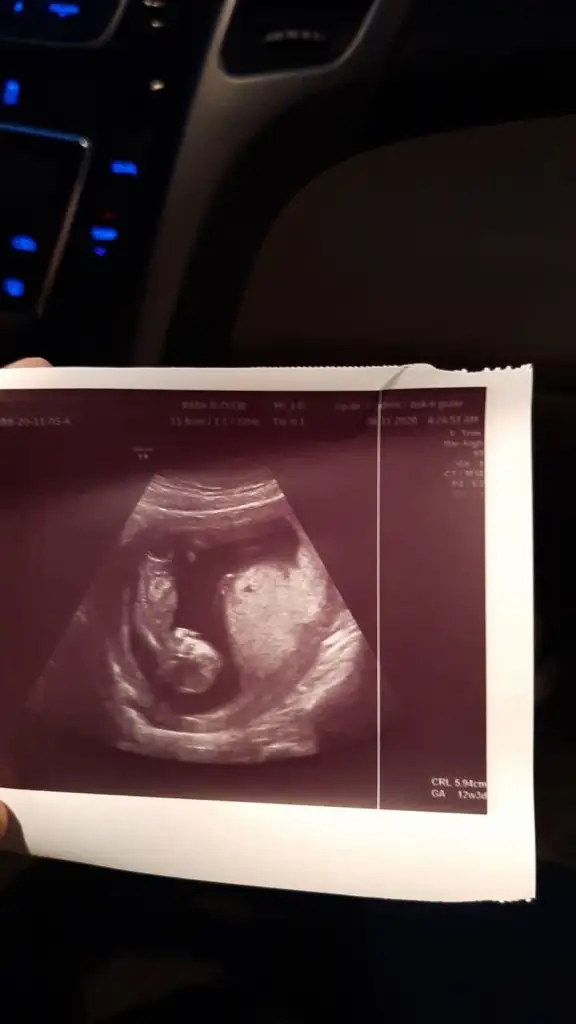

Dün yazdım ya kiza benziyor 12-13 haftayida paylaşın sonra gelip kız dediniz demeyin diyeBirde bana bakar Mısınız koz mi erkek mi Eki Görüntüle 2720009

Canım renkli ultrason mu bu çok net çıkmış bebeğin maşallahmerhaba tahmınınız nedır acaba??

yok kuzum benım degıl benımkı daha fasulyeCanım renkli ultrason mu bu çok net çıkmış bebeğin maşallah

Erkek gibiIkra meyra tahmin yapabilir misin canım?